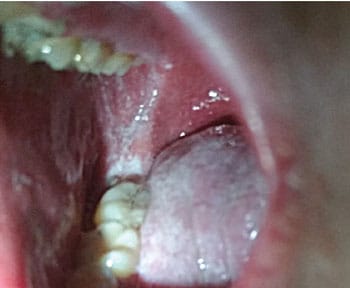

Clinical measles begins with small Koplik’s spots on the buccal mucosa, considered to be pathognomonic for the disease (Figure 2). The lesions can be numerous small, blue-white macules, also referred to as “grains of salt,” surrounded by erythema.9,10 Koplik’s spots occur 1 day to 2 days prior to the characteristic maculopapular skin rash; they may occur on the labial mucosa and soft palate in addition to the buccal mucosa, and in some cases, do not occur at all.10,11 Other oral manifestations associated with measles include candidiasis, necrotizing ulcerative gingivitis, and necrotizing stomatitis if the individual is suffering from severe malnutrition. Pitted enamel hypoplasia of developing permanent teeth may occur in severe cases of measles in early childhood. Enlargement of lingual and pharyngeal tonsils may be found during the course of illness.10